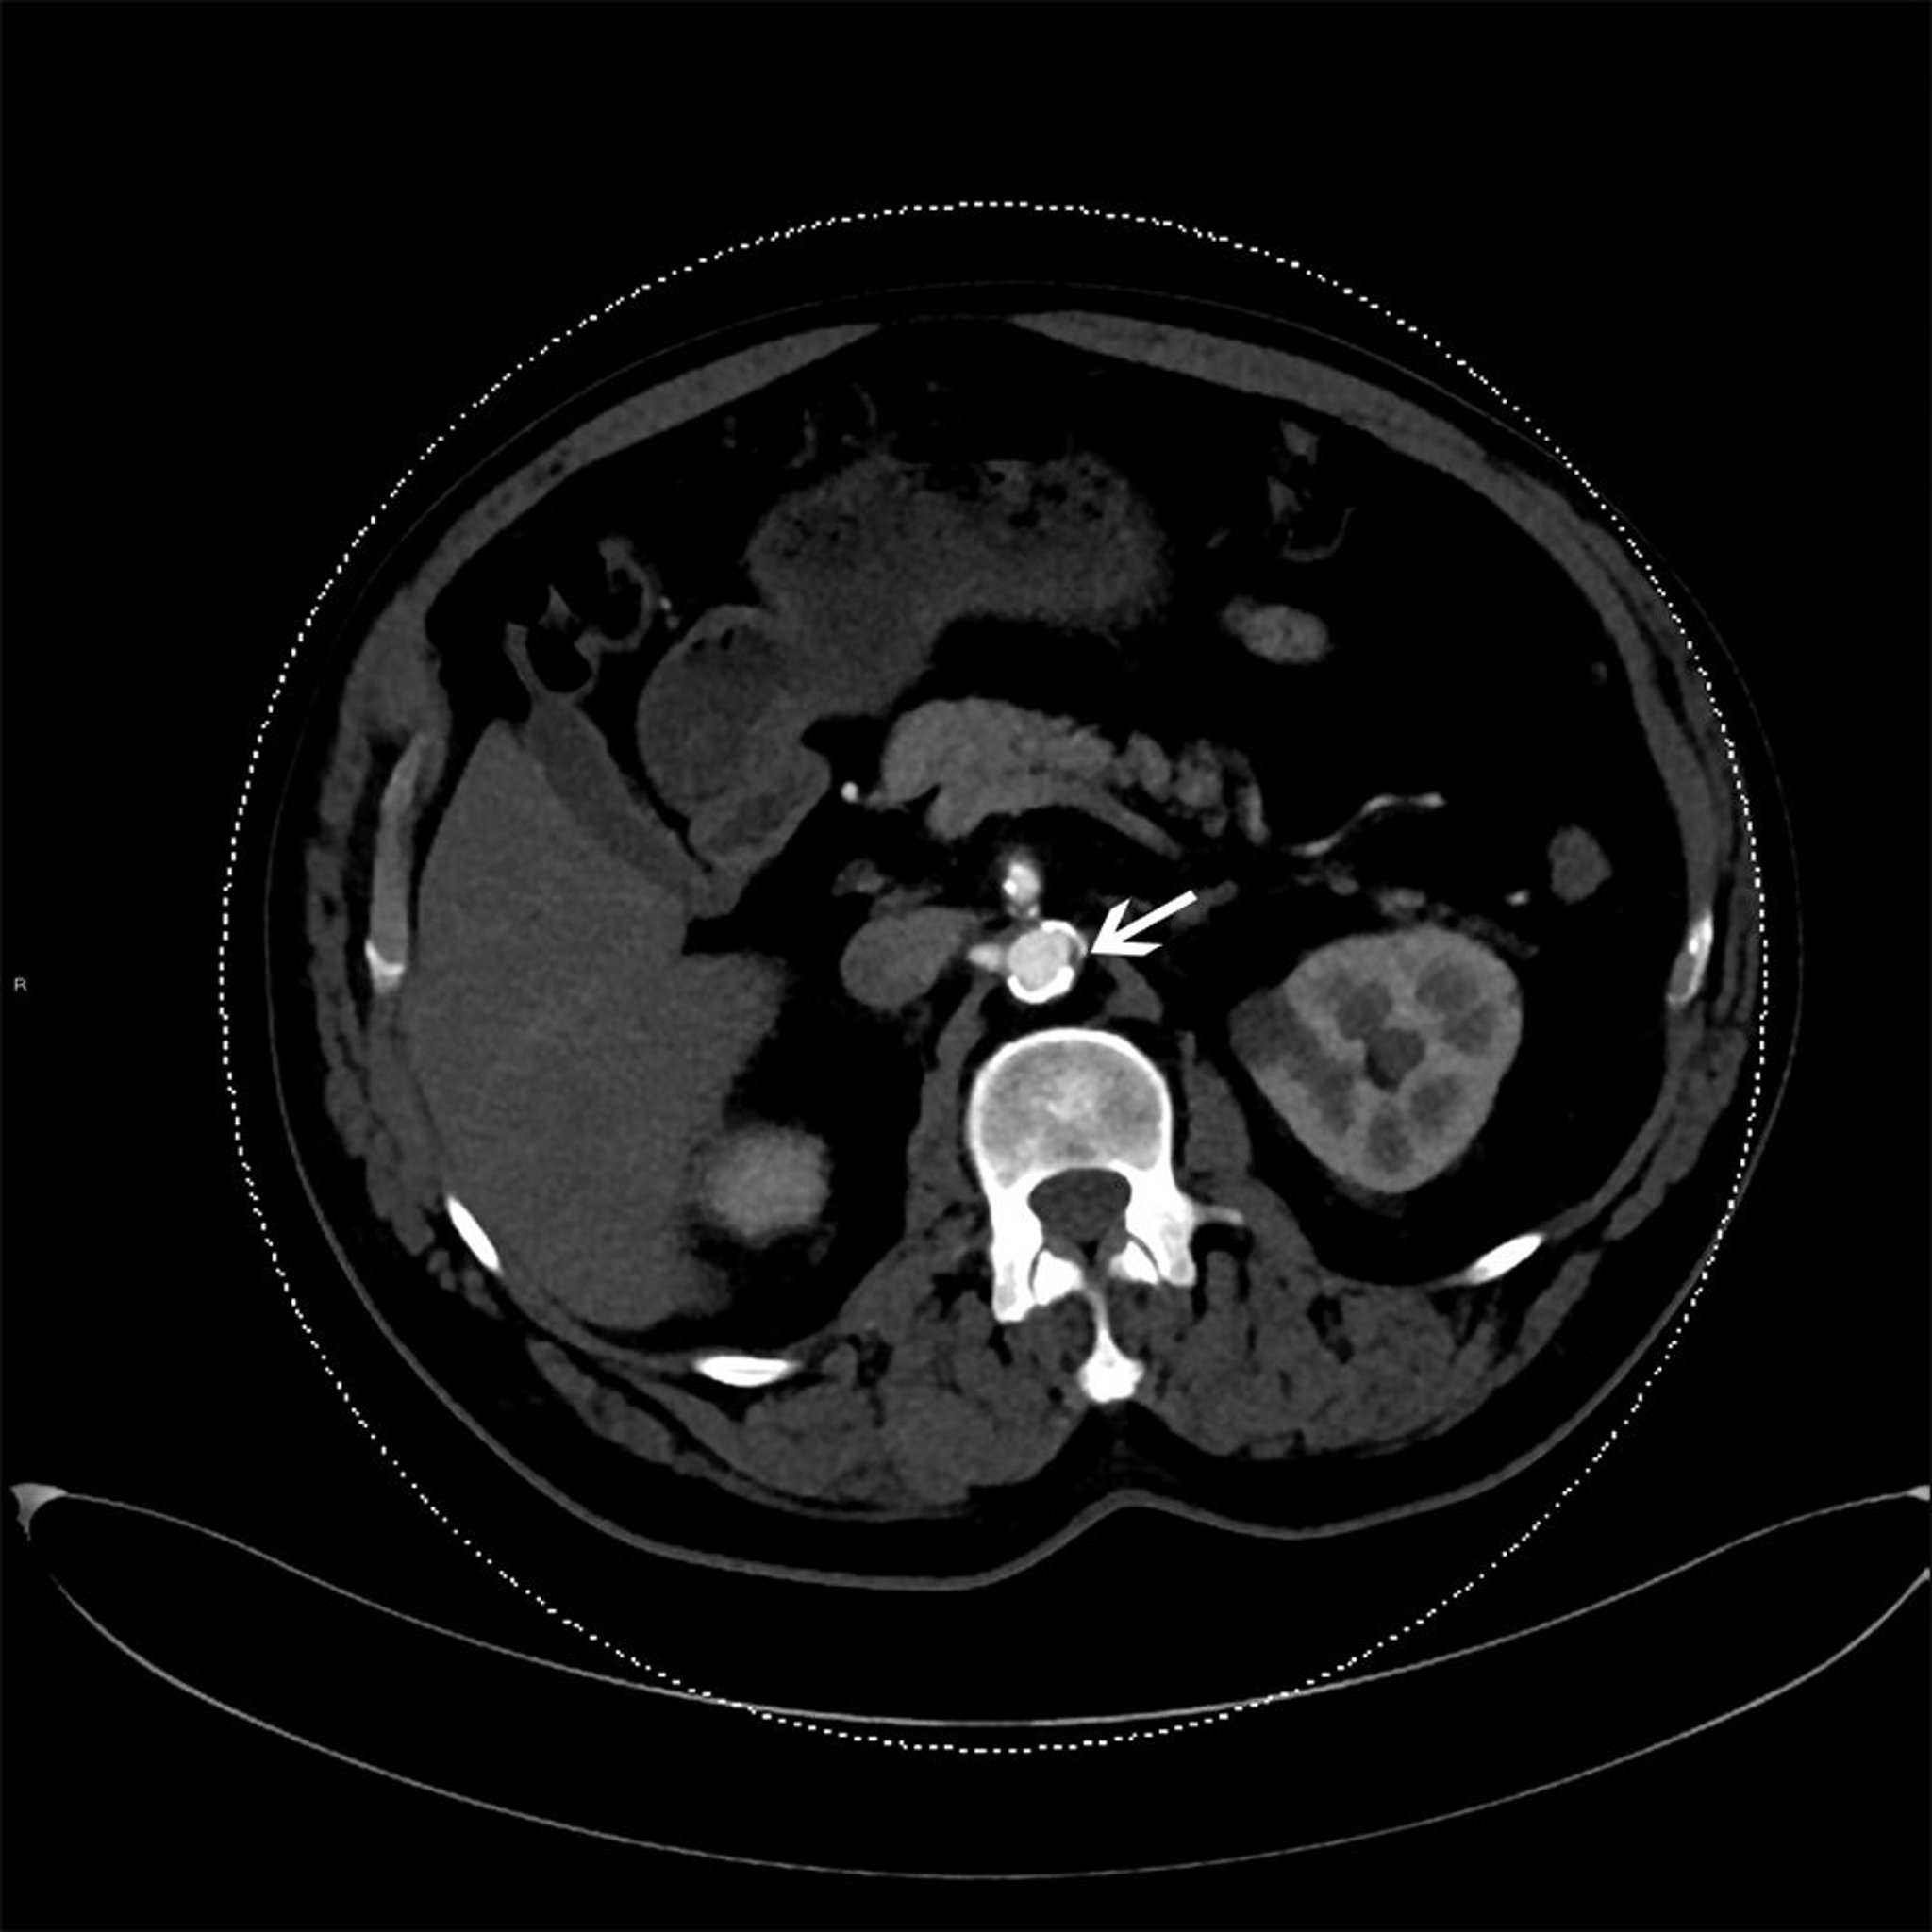

Esta tomografía computarizada con contraste muestra placa ateroesclerótica en la aorta descendente (flecha).